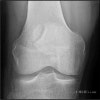

슬개골의 상외측에 분명한 골절선이 있지만, 통증이 없는 것이 원래부터 있었던 이분슬개골입니다.

X-ray에서 골절이라고 오해하기 딱 좋은 모양이지만 자세히 보면 경계부위가 약간 경화되어 있고 경계가 둥근 자갈이 막 깨어진 다르듯 차이가 납니다. 양측성인 경우가 있어 반대측도 같은 모양이라면 더욱 진단하기 용이합니다.

X-ray : 이분 슬개골(Bipartite patella)